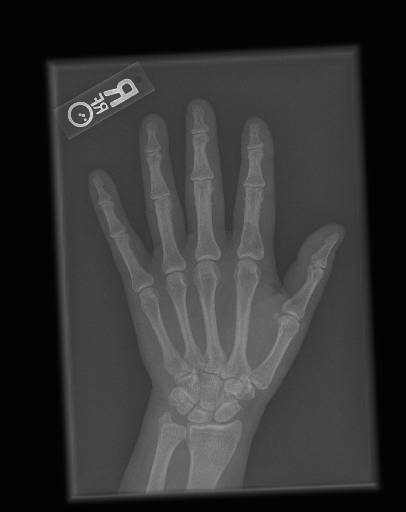

In this work, we focus on a subset of the MURA dataset [17] containing only hand images. In total, we have 5,543 images of 2,018 studies of 1,945 patients. Each study is labeled as negative or positive, where positive means that there was an anomaly diagnosed in this study. There are 521 positive studies, with a total of 1,484 images. Figure 1 shows some examples from the dataset. In summary, our contributions are as follows: